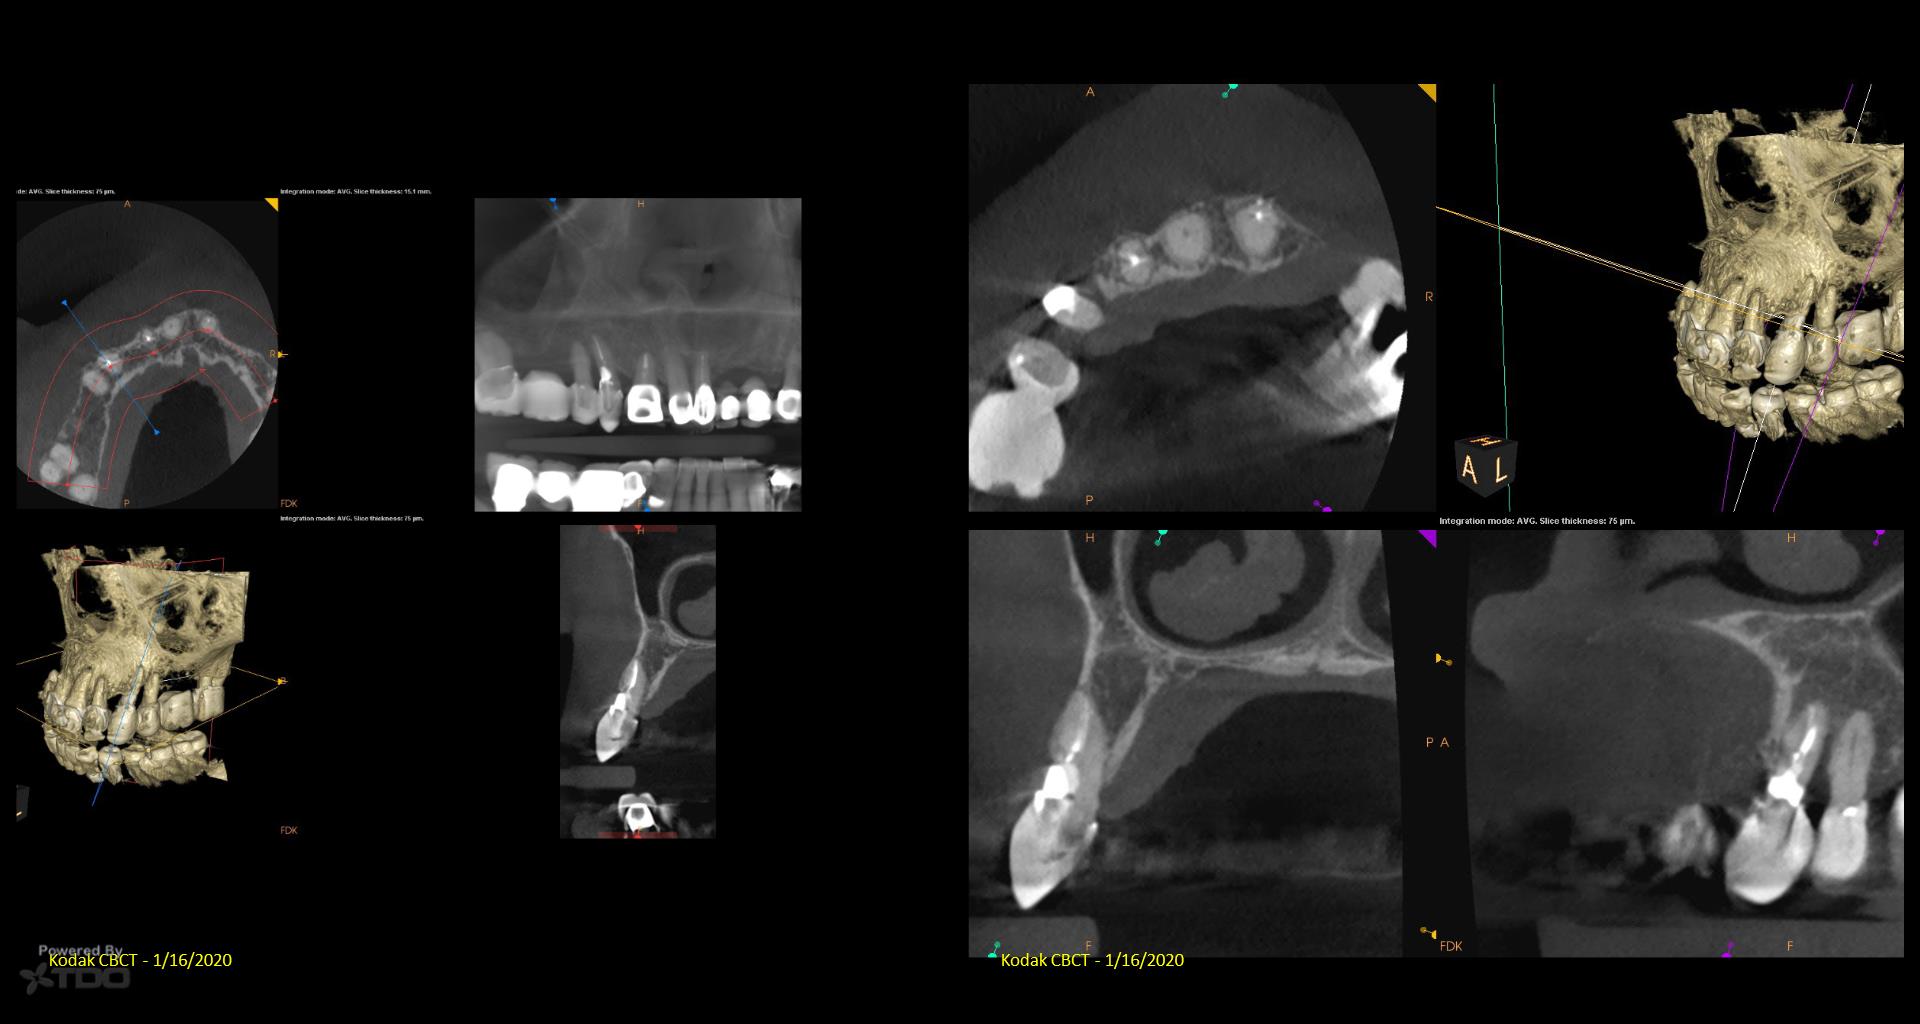

I posted this last month after the consult. There was mixed TDO advice—some said “do it” and others said monitor. Reluctantly, I did it Monday. I couldn’t really address the ECIR that was sub-osseous without removing way too much bone. I just hit it with the Pear Diamond as well as I could. Time will tell if it was a fool’s errand. I video’d the whole thing but don’t have the time to edit it. gbc